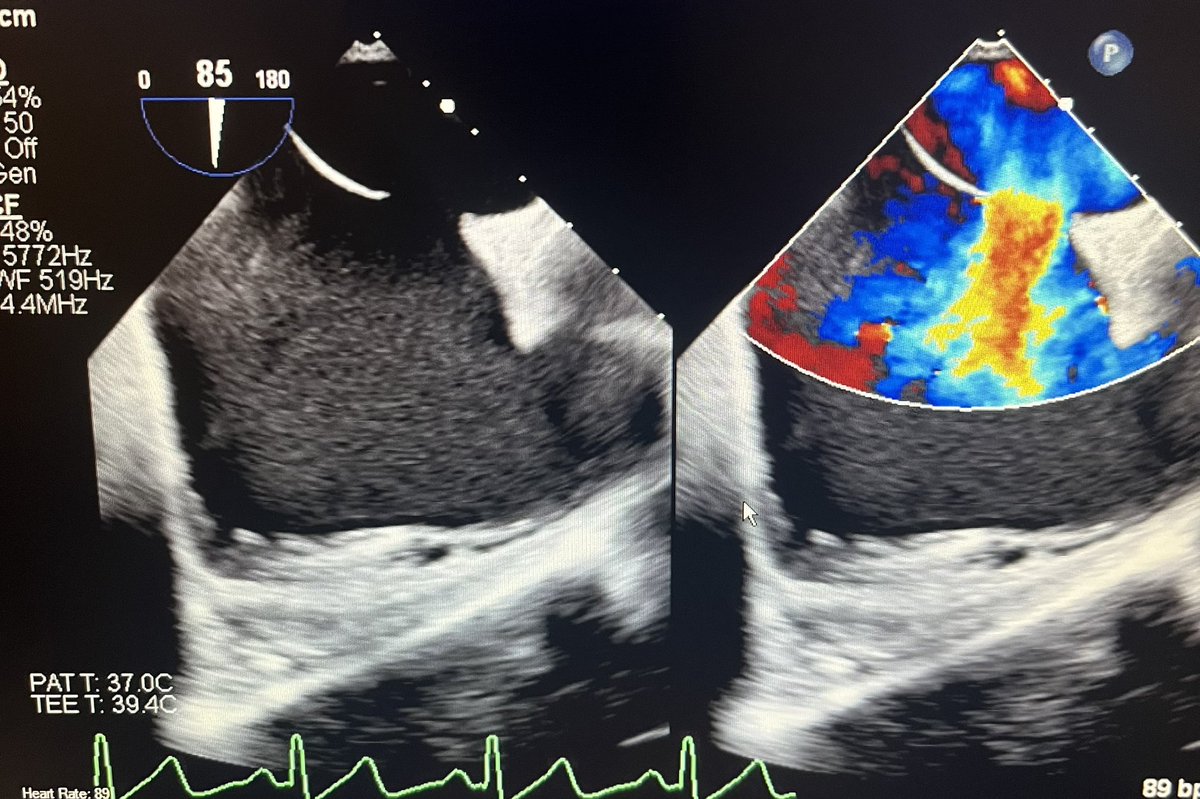

Excited to have placed the first occlutech ASD occluder @NortonChildrens in an adult with a moderate secundum ASD. Very smooth system and delivery. Great result! #ACHD #CHD #cardiotwitter #radialfirst #pedscards @Adam_Skaff @SohamDasguptaMD @FletcherVPowell